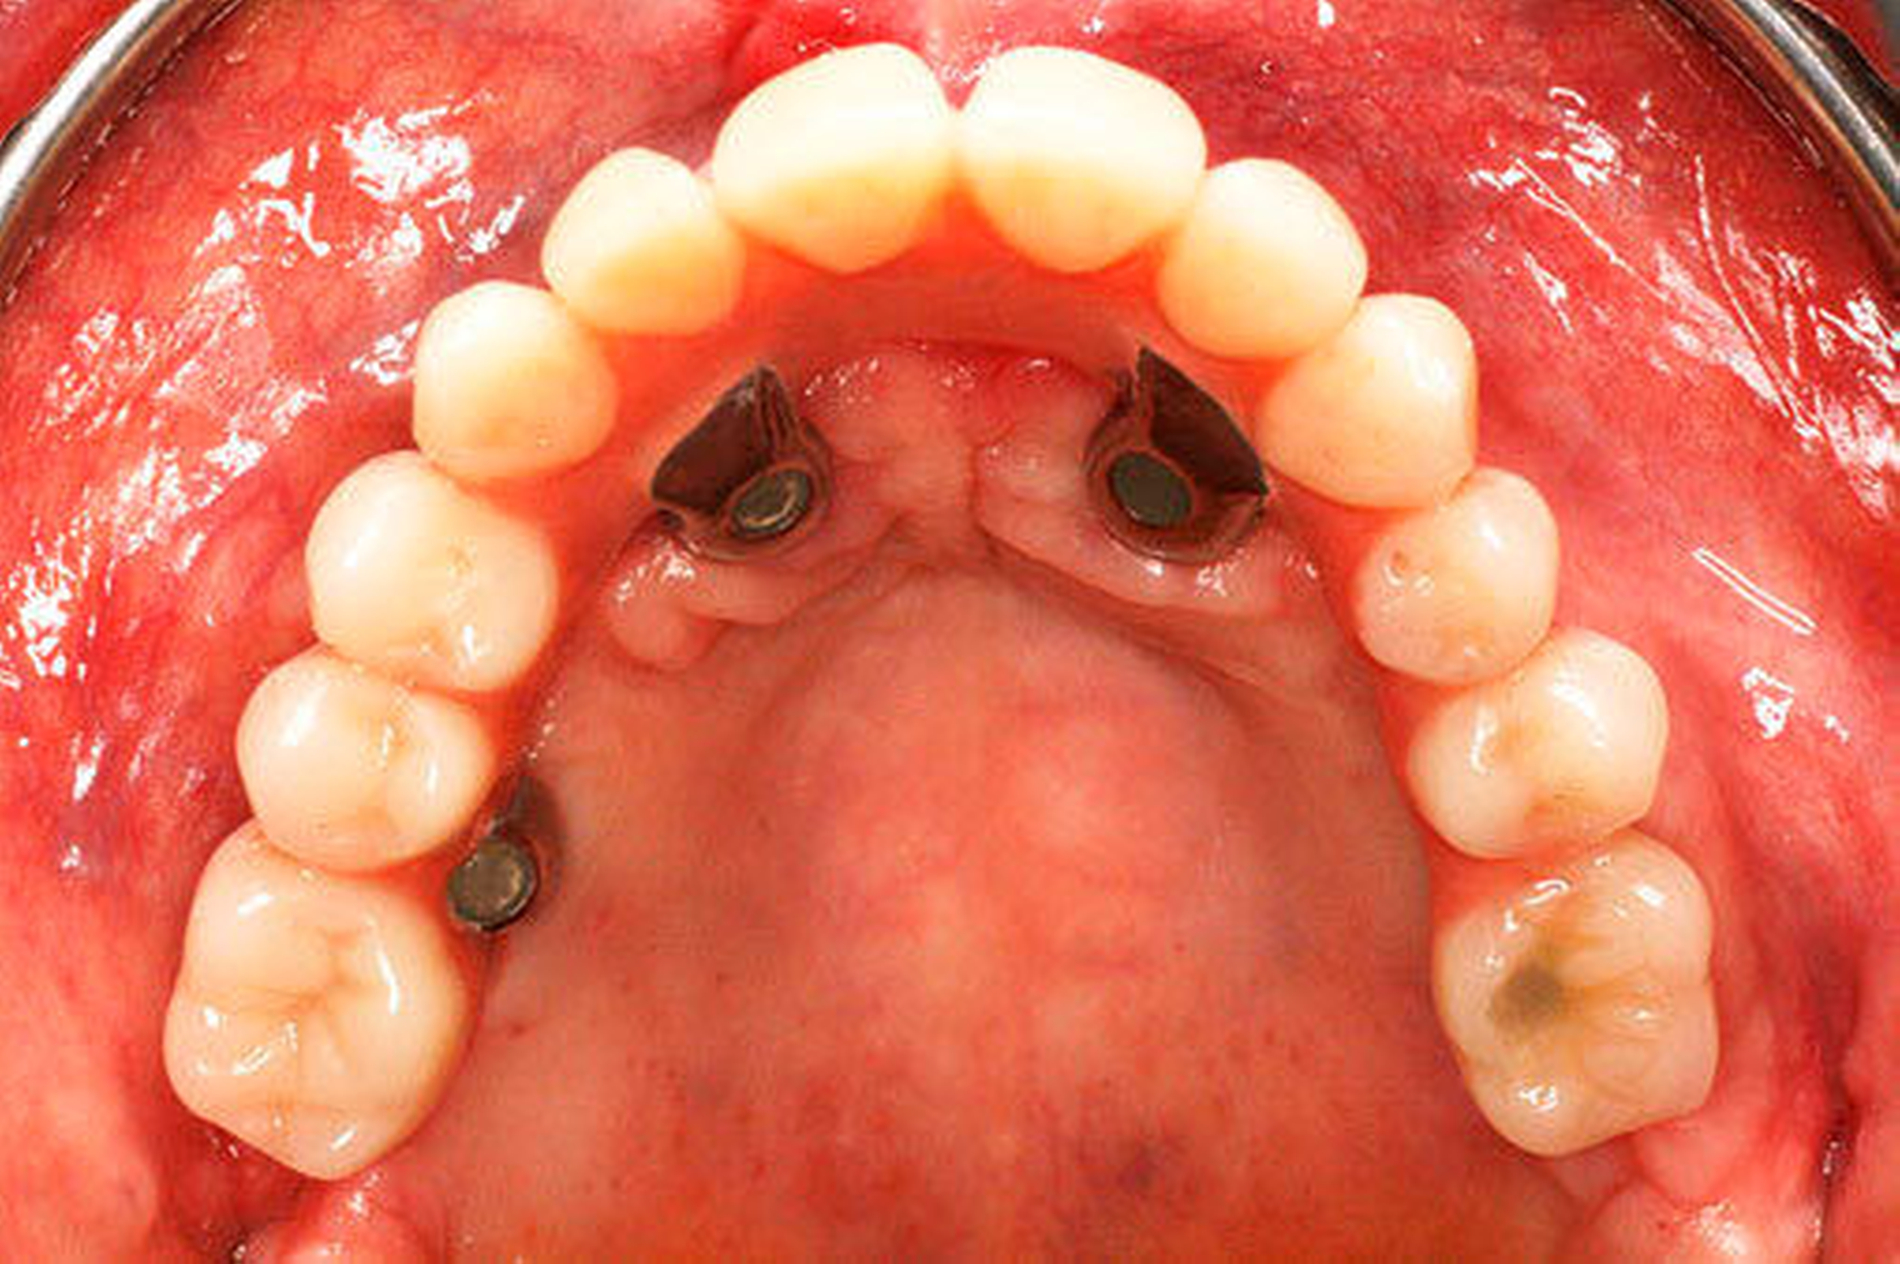

Entscheidend für den Erfolg dieses Konzepts ist die Hygienefähigkeit des Zahnersatzes. Die Basis des Zahnersatzes sollte konvex gestaltet werden und nur linear zum Kieferkamm Kontakt haben (Abbildung 1d). Diese Gestaltung erleichtert eine einfache Mundhygiene mit Interdentalbürsten und Zahnseide. Die Hygienefähigkeit einer All-on-4 Konstruktion ist somit vergleichbar mit einer Stegversorgung. Entscheidend für die Ästhetik ist die präoperative Feststellung der Lippenlachlinie. Diese entscheidet über die Resektionshöhe des Kieferkamms. Die Ästhetik wird bei dieser Versorgungsart ausschließlich über den Zahnersatz erreicht (Abbildung 1d). Die „rote Ästhetik“ kann durch die Verwendung von Prothesenkunststoff individuell und natürlich gestaltet werden. Der Zahnersatz ist bei diesem Konzept okklusal mit den Implantaten verschraubt (Abbildung 1c). Bei Notwendigkeit, zum Beispiel bei Reparaturen, kann dieser durch den Behandelnden leicht ab- genommen werden.

Eine erhebliche Erweiterung der Indikation des All-on-4 Konzeptes konnte durch den Einsatz von Zygoma-Implantaten erzielt werden. Zygoma-Implantate werden im Os zygomaticum verankert und erreichen auch in Situationen mit starker Kieferkammatrophie eine hohe Primärstabilität. Herkömmliche augmentative Verfahren können so vermieden werden. Zygoma-Implantate wurden zunächst bei Patienten mit besonderen Dysplasien im Kieferbereich und bei Tumorpatienten nach Resektion von Kieferanteilen eingesetzt. Balshi war einer der ersten Kliniker, der mit speziell gestalteten Implantaten entsprechende Fälle versorgte. Die Übertragung des All-on-4 Konzeptes auf Zygoma-Implantat-getragene Versorgungen ist insbesondere mit dem Namen Malavez verbunden, die sich sehr um diese Technik verdient gemacht hat. Dieses Konzept auf Zygoma-Implantaten wird angewendet in Fällen mit ausgeprägter Kieferkammatrophie im Oberkiefer (Abbildung 4a). Die Zygoma-Implantate werden in aller Regel in ITN inseriert. Lediglich ein externer Sinuslift ist als augmentative Maßnahme notwendig (Abbildungen 4b und c). Durch dieses Vorgehen können aufwändige augmentative Verfahren umgangen werden. Die prothetische Versorgung der Zygoma-Implantate entspricht dem Vorgehen wie beim All-on-4 Konzept und erfolgt einen Tag postoperativ. Erreicht wird, wie beim ursprünglichen All-on-4 Konzept, eine festsitzende Sofortversorgung (Abbildungen 3 und 4d).